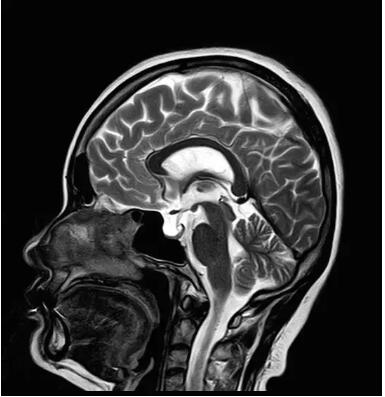

見所未見 微小腫瘤無處遁藏——

“螢火蟲”成像技術(shù) 顱內(nèi)腫瘤微小病灶檢出新發(fā)現(xiàn)

此技術(shù)主要用于神經(jīng)系統(tǒng)惡性腫瘤,以及其他腫瘤腦轉(zhuǎn)移瘤篩查。傳統(tǒng)情況下做腫瘤腦轉(zhuǎn)移篩查,很容易漏掉5mm以下小病灶,臨床發(fā)現(xiàn)后干預(yù)治療比較晚,要實現(xiàn)2mm高空間分辨率和超薄層全腦掃描在保證信噪比的情況下需要很長時間大概十多分鐘,而且薄層增強序列顱內(nèi)血管呈高亮信號,會干擾顱內(nèi)小病灶的觀察,血管和小病灶區(qū)分困難。佳能”螢火蟲”成像技術(shù)既可以實現(xiàn)高空間分辨率和超薄層(最薄可實現(xiàn)0.2mm)全腦掃描,掃描時間短,2-3分鐘即可實現(xiàn)全腦3D掃描,同時避免了血管高亮信號的干擾,對顱內(nèi)原發(fā)或繼發(fā)的微小腫瘤檢查有重大意義。“螢火蟲”成像技術(shù)具有磁敏感效應(yīng),對于亞急性血敏感敏感,可以區(qū)分出血和強化的腫瘤。